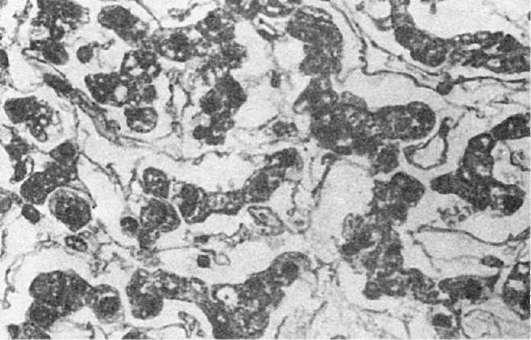

воспалении слизистых оболочек, которые также становятся полнокровными, к экссудату примешиваются слизь и спущенные клетки эпителия, возникает серозный катар слизистой оболочки (см. ниже описание катарального воспаления). В печени жидкость накапливается в перисинусоидальных пространствах (рис. 65), вмиокарде - между мышечными волокнами, в почках - в просвете клубочковой капсулы. Серозное воспалениекожи, например при ожоге, выражается образованием пузырей, возникающих в толще эпидермиса, заполненных мутноватым выпотом. Иногда экссудат накапливается под эпидермисом и отслаивает его от подлежащей ткани с образованием крупных пузырей.

Рис.

65. Серозный гепатит